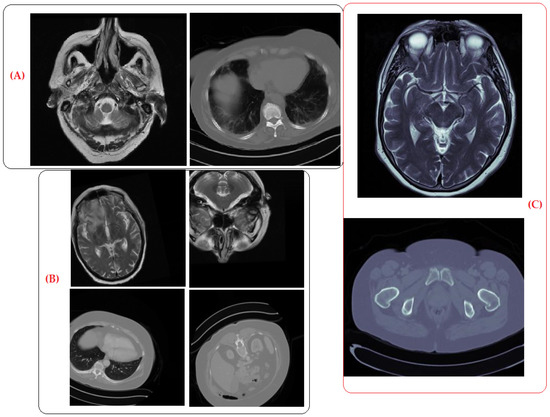

To evaluate the synthesized data of brain and kidney tumors, we tasked two experienced radiologists with categorizing real, augmented, and synthetic images for both datasets. This experiment aimed to determine whether radiologists could distinguish between the real images and synthetic images generated by the DCGAN. Consistent classification outcomes would indicate the utility of the artificial data for training machine learning models.

• Evaluation Process:

• Image Presentation: The experts were shown a randomized mix of real primary images, augmented images, and synthetic images. Each set included the following:

• Original brain tumor images (MRI);

• Augmented brain tumor images (MRI);

• Synthetic brain tumor images generated by the DCGAN;

• Original kidney tumor images (MRI);

• Augmented kidney tumor images (MRI);

• Synthetic kidney tumor images generated by the DCGAN.

• Task: The radiologists were asked to classify each image as either real (original/augmented) or synthetic.

• Scoring: The accuracy of their classifications was recorded, with a focus on the difference in performance between real and synthetic images.

• Results:

• Expert 1: accurately recognized both real and synthetic brain and kidney tumors with a 20% success rate.

• Expert 2: accurately classified the real, augmented, and synthetic brain and kidney images with a 25% success rate for each category.

Both experts achieved comparable classification performances for real, augmented, and synthetic images. This indicates that the synthetic images generated using the DCGAN have significant similarity to real and augmented images, thus validating their potential utility for training machine learning models.

Sample Images: To provide further clarity on the quality of the synthetic images, we include sample images in Figure 10.

The comparable performance of the radiologists in categorizing real, augmented, and generated images confirmed the efficacy of the DCGAN in producing realistic synthetic images. The DCGAN not only generated new images but also provided notable benefits, such as the ability to generate synthetic images with diverse variations, enhance image qualities, and streamline the training process by eliminating artifacts. These images can be confidently used for training machine learning models, enhancing the diversity and robustness of the datasets to enhance the accuracy of model performance.